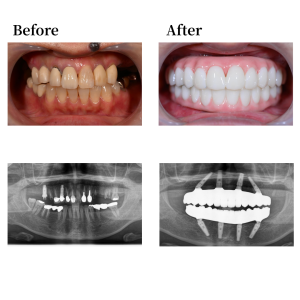

上顎骨の形状を整え、12,22,25の位置にザイゴマインプラ座52度傾斜埋入。15 の位置にザイゴマインプラントを60度傾斜埋入。下顎も形状を整え、45, 42, 32, 35の位置にそれぞれオールオン4インプラントを埋入。 42, 32の位置に、0度垂直埋入、45, 35の位置に17度傾斜埋入。その後、マルチユニットアバットメントで角度補正を行い、プロビジョナルレストレーション(審美的な仮歯)を装着した。

上下顎はUTジルコニアで構成された、フルジルコニアブリッジでファイナルレストレーションとした。焼成されたジルコニアはステインテクニックで着色した。シェードカラーはA1。